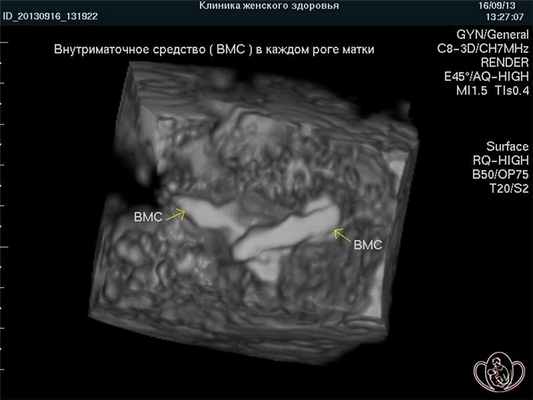

Ответ: При двурогой матке ВМС требуется устанавливать в каждый рог при условии их полноценного развития. Эффективность ВМС не отличается от типичного случая.3D-фото: двурогая матка. Внутриматочное средство (ВМС) установлено в обоих рогах матки ![Двурогая матка]()